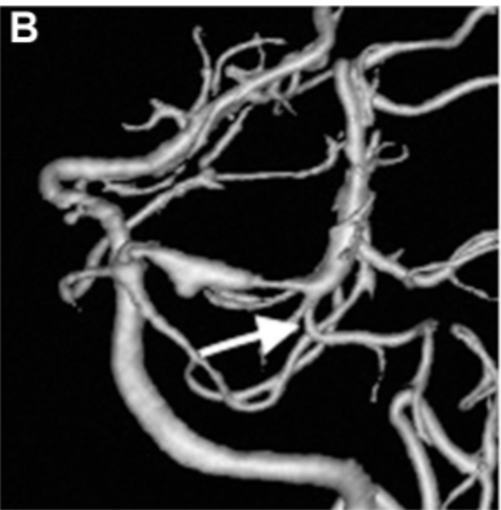

▼PTA在动脉瘤远端分支(图2A和2B)。予以右侧颞下入路手术,切除梭状回的一小部分被软膜,暴露动脉瘤顶端。随后,暴露动脉瘤的近端和远端颈,并识别PTA和P3段。

▼P3段被选为搭桥血管位置(图2C和2D)。如上所述,教授进行了STA-P3旁路手术并孤立动脉瘤。为了夹住动脉瘤,Kawashima教授使用了直长夹和有孔夹的组合,以避免P3段和PTA扭结。